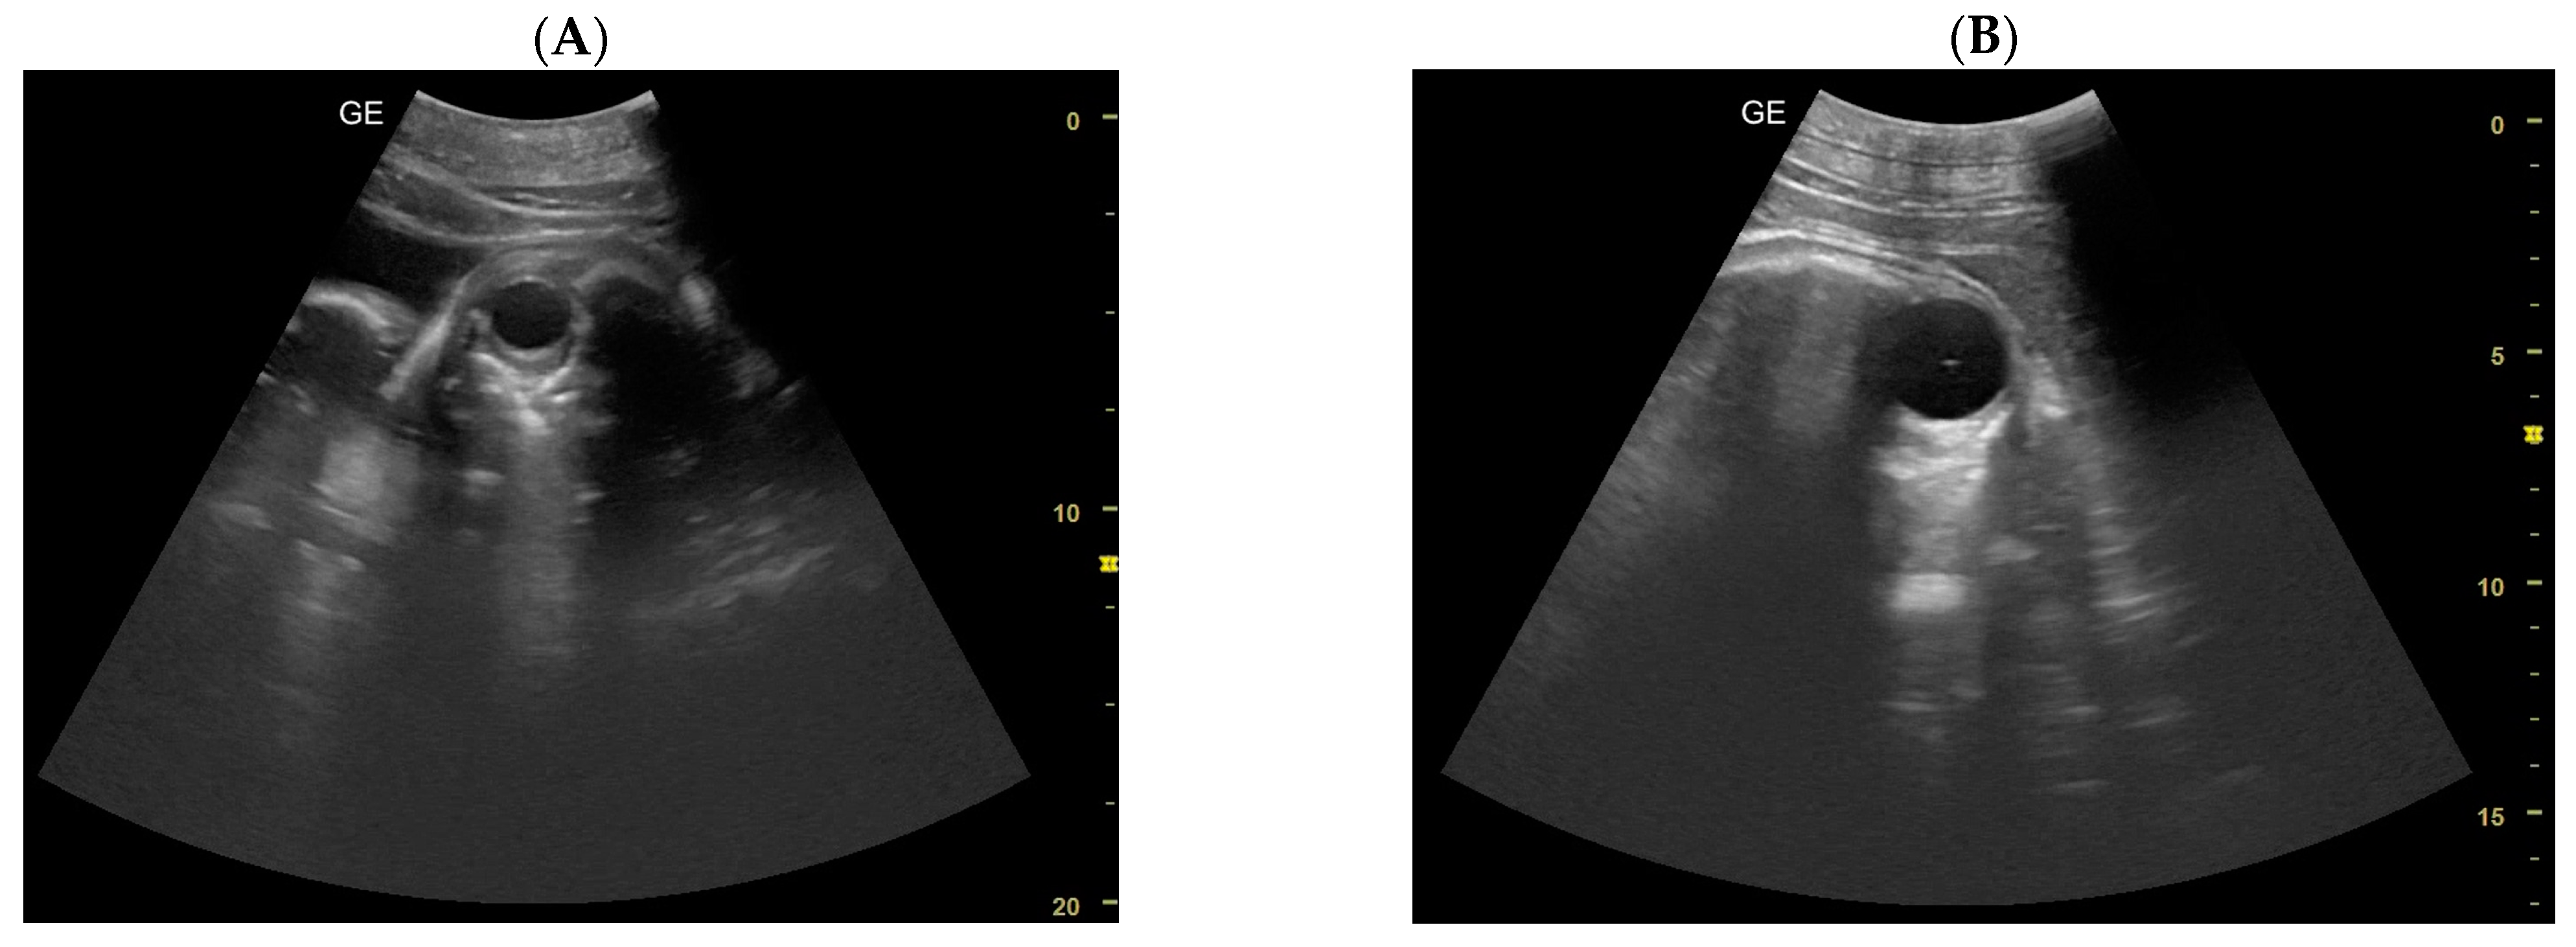

- Day 113 ± 4 post-ovulation: The embryonic vesicle was first recognizable in the uterine cavity as a roundish structure with an average diameter of 1.71 cm with an anechoic content. In addition, it is possible to recognize the embryo inside it as an elongated hyperechoic structure (Figure 2). Thanks to these findings, it has been possible to make a diagnosis of pregnancy.